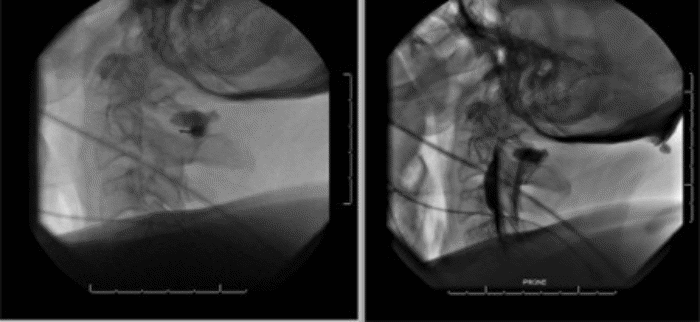

To localize the potential leak in the dura matter, a cervical puncture (C1-C2) computed tomography (CT) myelogram was performed (Figure 2). Fluoroscopy showed a rapid opacification of the ventral cervical epidural collection. While this obscured the exact location of the defect, it suggested a defect close to the contrast injection site at C2. Furthermore, just superior to the level of the left C3 pedicle, a hyperdense extradural focus was seen on the post myelography CT scan, which suggested an area of traumatic ectopic calcification, potentially secondary to an initial dural injury.

Figure 2. Cervical Myelogram Following C1-C2 Puncture. Published with Permission.

Immediate communication of injected contrast into the ventral pseudomeningocele from C2 to C4